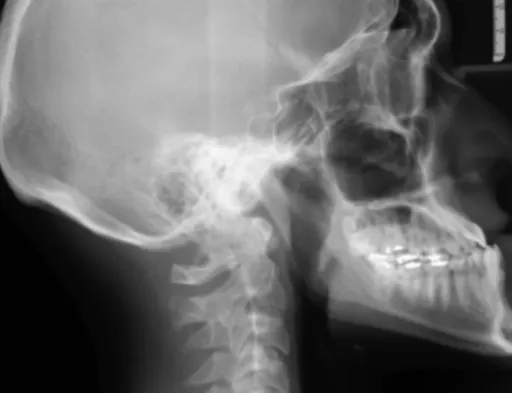

3. 턱관절 장애의 신호일 수도 있어요

의외로 턱관절에 문제가 생겨도 관자놀이 쪽으로 통증이 느껴질 수 있어요. 입을 벌리거나 다물 때 턱에서 소리가 나거나, 턱이 부자연스럽게 움직인다면 '턱관절 장애' 를 의심해 보고 관련 진료를 받아보시는 게 좋아요.